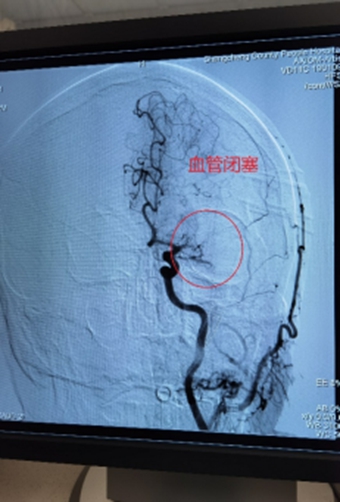

1、左侧颈内动脉末端闭塞,急诊导管抽栓+支架拉栓1例;

0009.jpg

0010.jpg

0011.jpg

0012.jpg